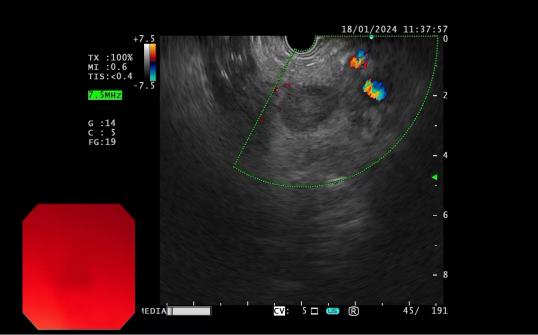

4d818f53b089499c860884ad0d9dab6c.Jpega62e29074df94ee9a5dace0b932c125d.Jpeg

發(fā)現(xiàn)內(nèi)源性低回聲病灶        實(shí)時(shí)超聲引導(dǎo)下對(duì)病灶的細(xì)針穿刺活檢

內(nèi)鏡超聲引導(dǎo)下細(xì)針穿刺抽吸術(shù)(EUS-FNA):治療對(duì)于性質(zhì)不明的胰腺實(shí)性占位性病變;對(duì)于經(jīng)CTMRI或 EUS 等檢查不能確定性質(zhì)的胰腺囊性病變;對(duì)于消化道毗鄰組織中性質(zhì)不明的占位性病變或淋巴結(jié)腫大(如縱隔、上腹部等部位病變);長(zhǎng)徑>2cm需要手術(shù)切除但具有高手術(shù)切除風(fēng)險(xiǎn),或不能切除的消化道上皮下腫瘤的鑒別診斷。